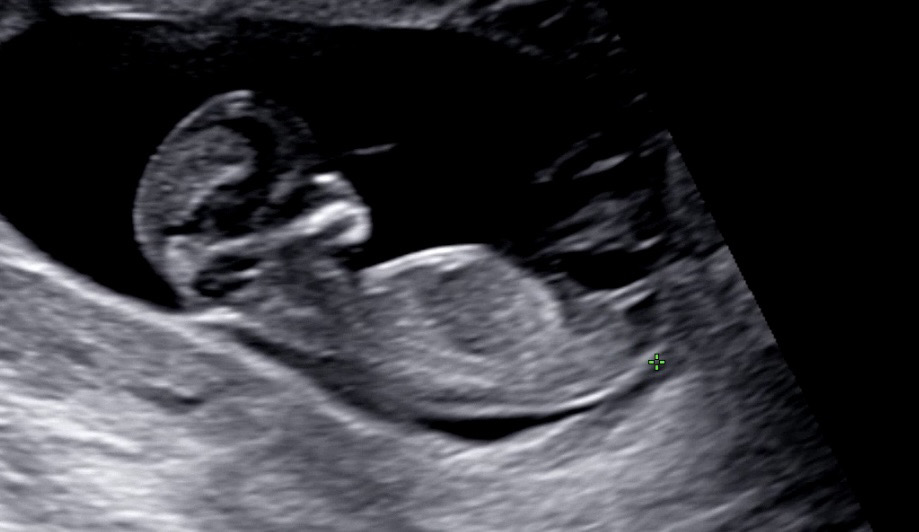

각도법 고수님들 한번만 봐주세용🥹

이사진으로 알 수 있는지 모르겠지만 너무 궁금해서요 ㅎㅎ 아들일까요 딸일까요??

이 사진은 아들같아욤!